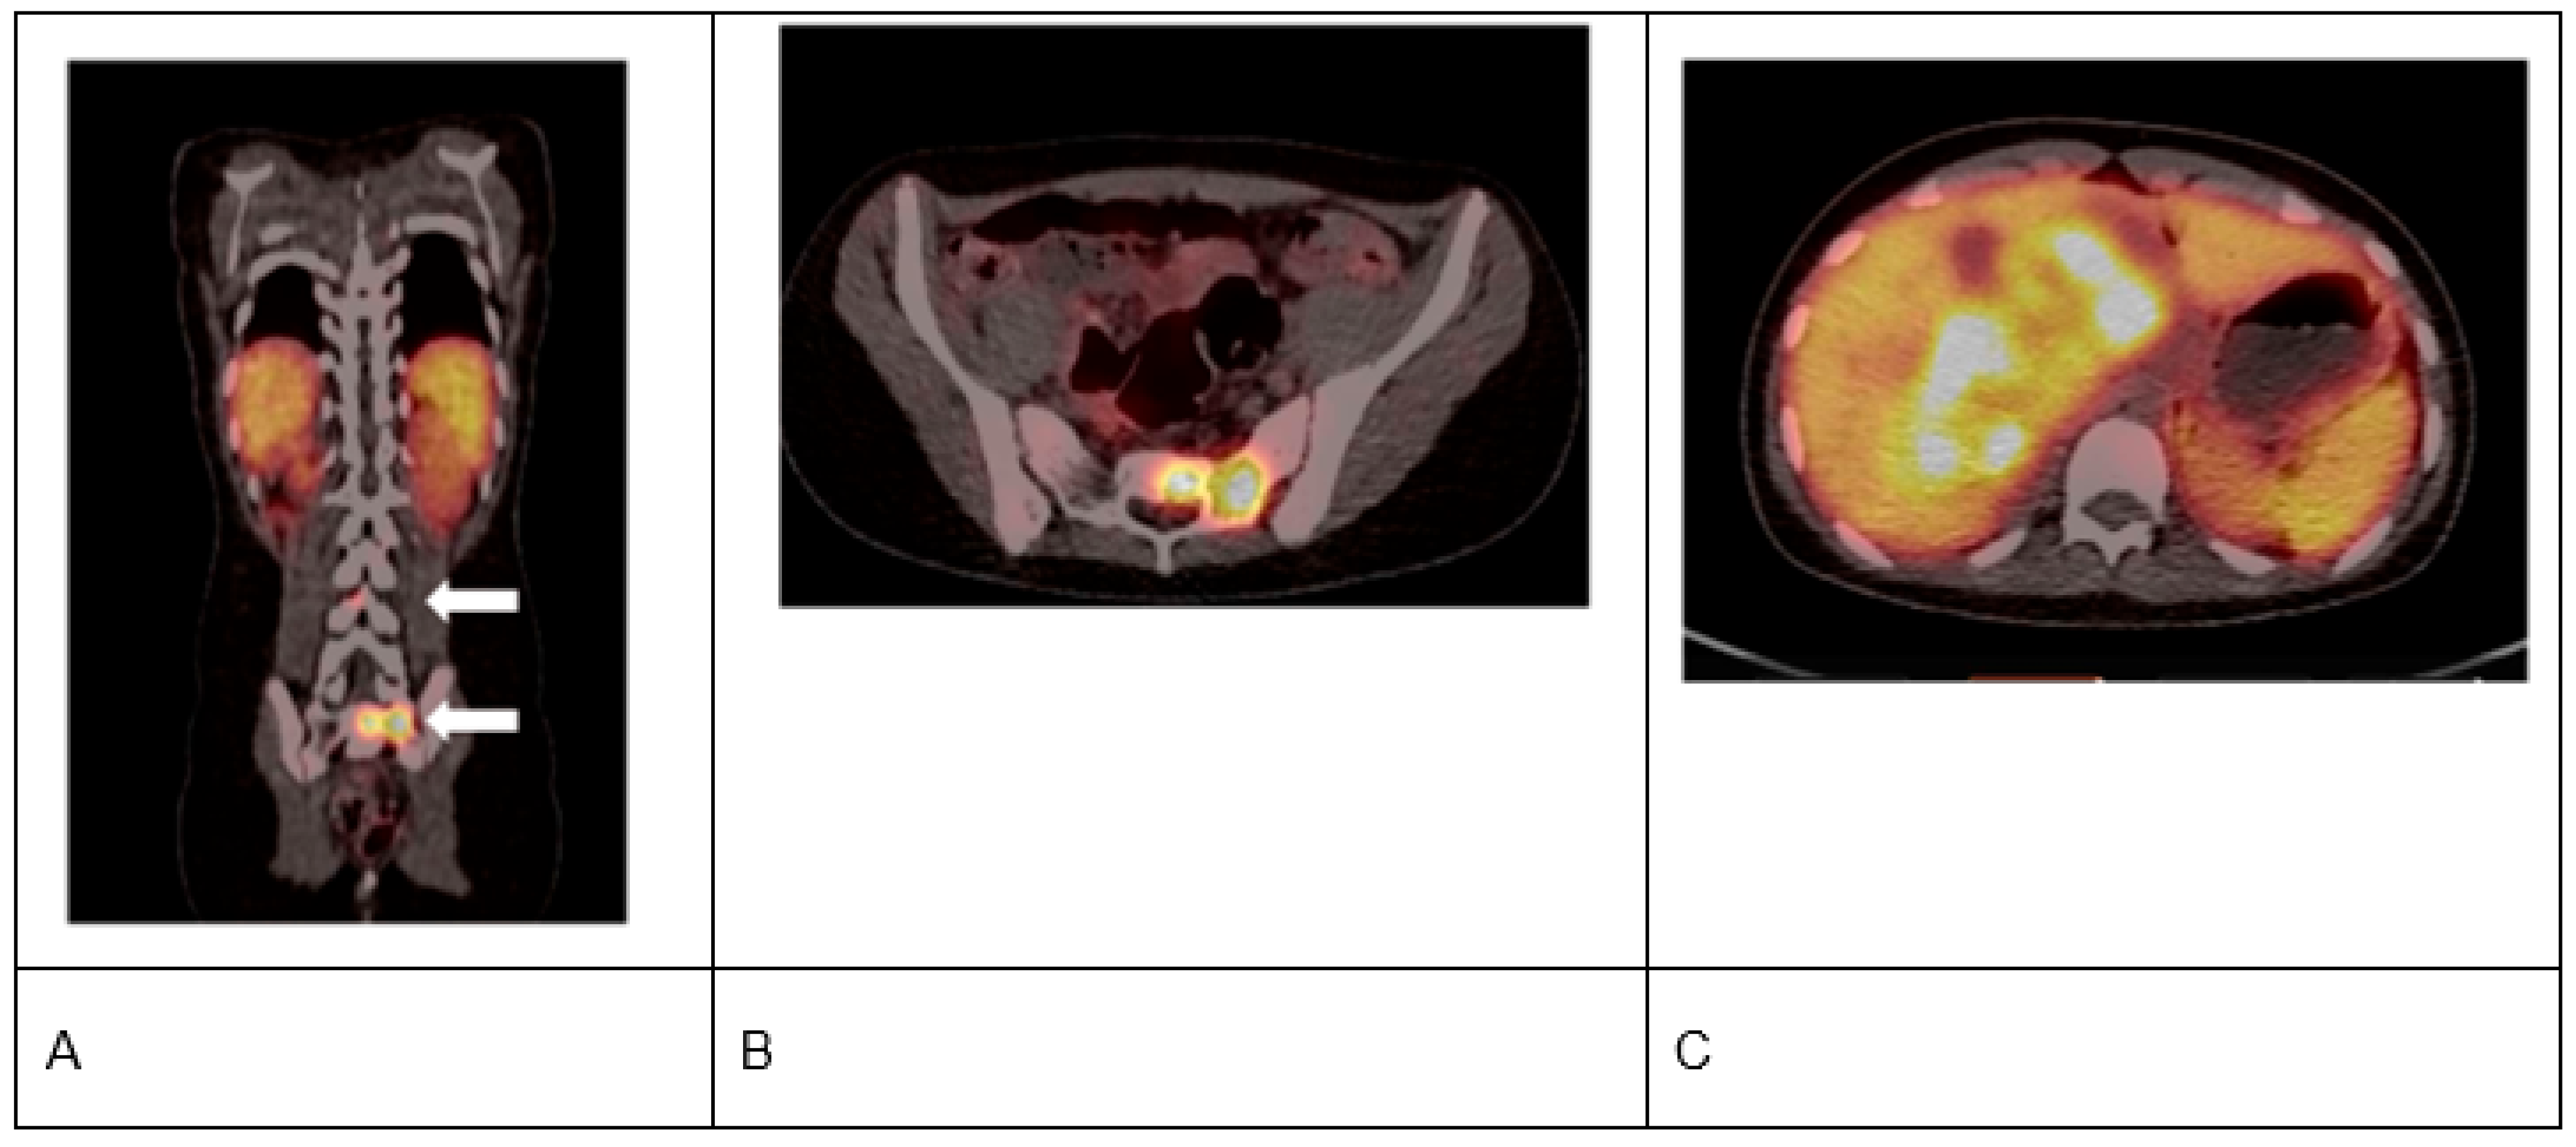

- Gains, J.E.; Aldridge, M.D.; Mattoli, M.V.; Bomanji, J.B.; Biassoni, L.; Shankar, A.; Gaze, M.N. 68Ga-DOTATATE and 123I-mIBG as imaging biomarkers of disease localisation in metastatic neuroblastoma: Implications for molecular radiotherapy. Nucl. Med. Commun. 2020, 41, 1169–1177. [Google Scholar] [CrossRef]

- Kong, G.; Hofman, M.S.; Murray, W.K.; Wilson, S.; Wood, P.; Downie, P.; Super, L.; Hogg, A.; Eu, P.; Hicks, R.J. Initial experience with gallium-68 DOTA-octreotate PET/CT and peptide receptor radionuclide therapy for pediatric patients with refractory metastatic neuroblastoma. J. Pediatr. Hematol. Oncol. 2016, 38, 87–96. [Google Scholar] [CrossRef]